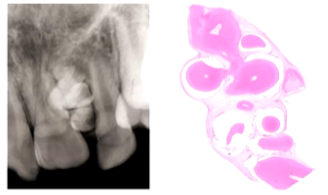

Describe the Follicular Pattern of an Ameloblastoma (3)

1) Columnar Ameloblast Like Cells at the Periphery

2) Stellate Reticulum-Like area in the Centre

3) The Epithelium resembles the enamel organ, cysts form in the Stellate Reticulum like Areas.

Describe the Plexiform Pattern of an Ameloblastoma (3)

1) Columnar Ameloblasts - like cells forming Cords

2) Little or No Stellate Reticulum like areas

3) Cysts form in the Stroma